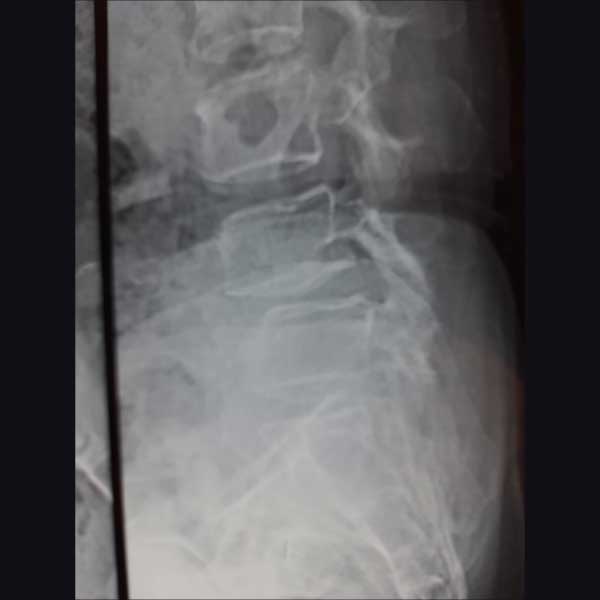

A female patient, aged 55 years had been diagnosed to have Degenerative Spondylolysis with SpondylolisthesisL4-L5 with disc prolapse and neurological painful claudication She was treated operatively with Posterior fixation & Anterior fusion & bone grafting with cage insertion.

Pre-Operative Lateral View

PreopLateral